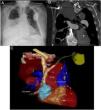

Ante la sospecha de perforación cardíaca secundaria al DAI por las imágenes de la radiografía de tórax (fig. 1A), se realizó tomografía computarizada (TC) de tórax (fig. 1B y fig. 1C) donde se observó perforación de pared auricular derecha por cable del DAI con enclavamiento del mismo en parénquima pulmonar inferior derecho. Se asociaba marcado derrame pleural derecho y discreto neumotórax apical ipsilateral. Se derivó a centro de referencia para tratamiento, donde se realizó retirada del electrodo por vía percutánea sin complicaciones.

A) Arriba a la izquierda, radiografía de tórax en la que se observa el electrodo de la aurícula derecha con su extremo distal más lateralizado de lo que debería, con derrame pleural ipsilateral asociado. B) Arriba a la derecha, corte coronal donde se observa el electrodo enclavado en el parénquima pulmonar y derrame pleural derecho. C) Abajo, reconstrucción en 3D de la tomografía computarizada en la que puede observarse el electrodo del DAI en el momento de la perforación de la aurícula derecha. A la derecha, A. Pulmonar: arteria pulmonar.